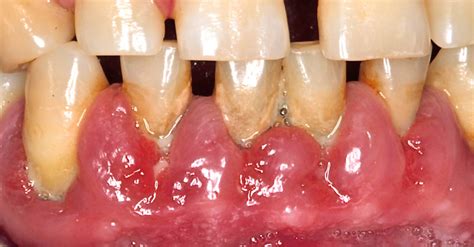

Ejemplo de tratamiento quirúrgico para la hiperplasia gingival.

- Intervención quirúrgica: Si la terapia no quirúrgica resulta insuficiente, el dentista puede recurrir a la gingivectomía o a la cirugía plástica mucogingival. En casos más severos y cuando no sea posible aplicar las medidas anteriores, puede estar indicada la escisión del exceso de tejido y restauración del contorno gingival mediante una . La operación no suele tener ninguna contraindicación particular, y muestra un buen éxito cuando se utilizan técnicas especiales como el láser, que reduce la hemorragia local. La gingivectomía convencional con bisturí, eliminando tejido hiperplásico hasta obtener contorno gingival fisiológico, representa técnica tradicional efectiva. Indicada principalmente en hiperplasias fibróticas establecidas con pseudobolsas sin pérdida de inserción significativa. Las técnicas quirúrgicas con láser (diodo, CO2, Er:YAG) ofrecen ventajas como hemostasia simultánea, menor dolor postoperatorio, reducción de tiempo operatorio y efecto antimicrobiano adicional. La electrocirugía proporciona corte y coagulación simultáneos, resultando útil en tejidos muy vascularizados. Existe el riesgo de recidivas si no se retira la medicación que provocó el agrandamiento gingival en hasta un 40% de los pacientes.